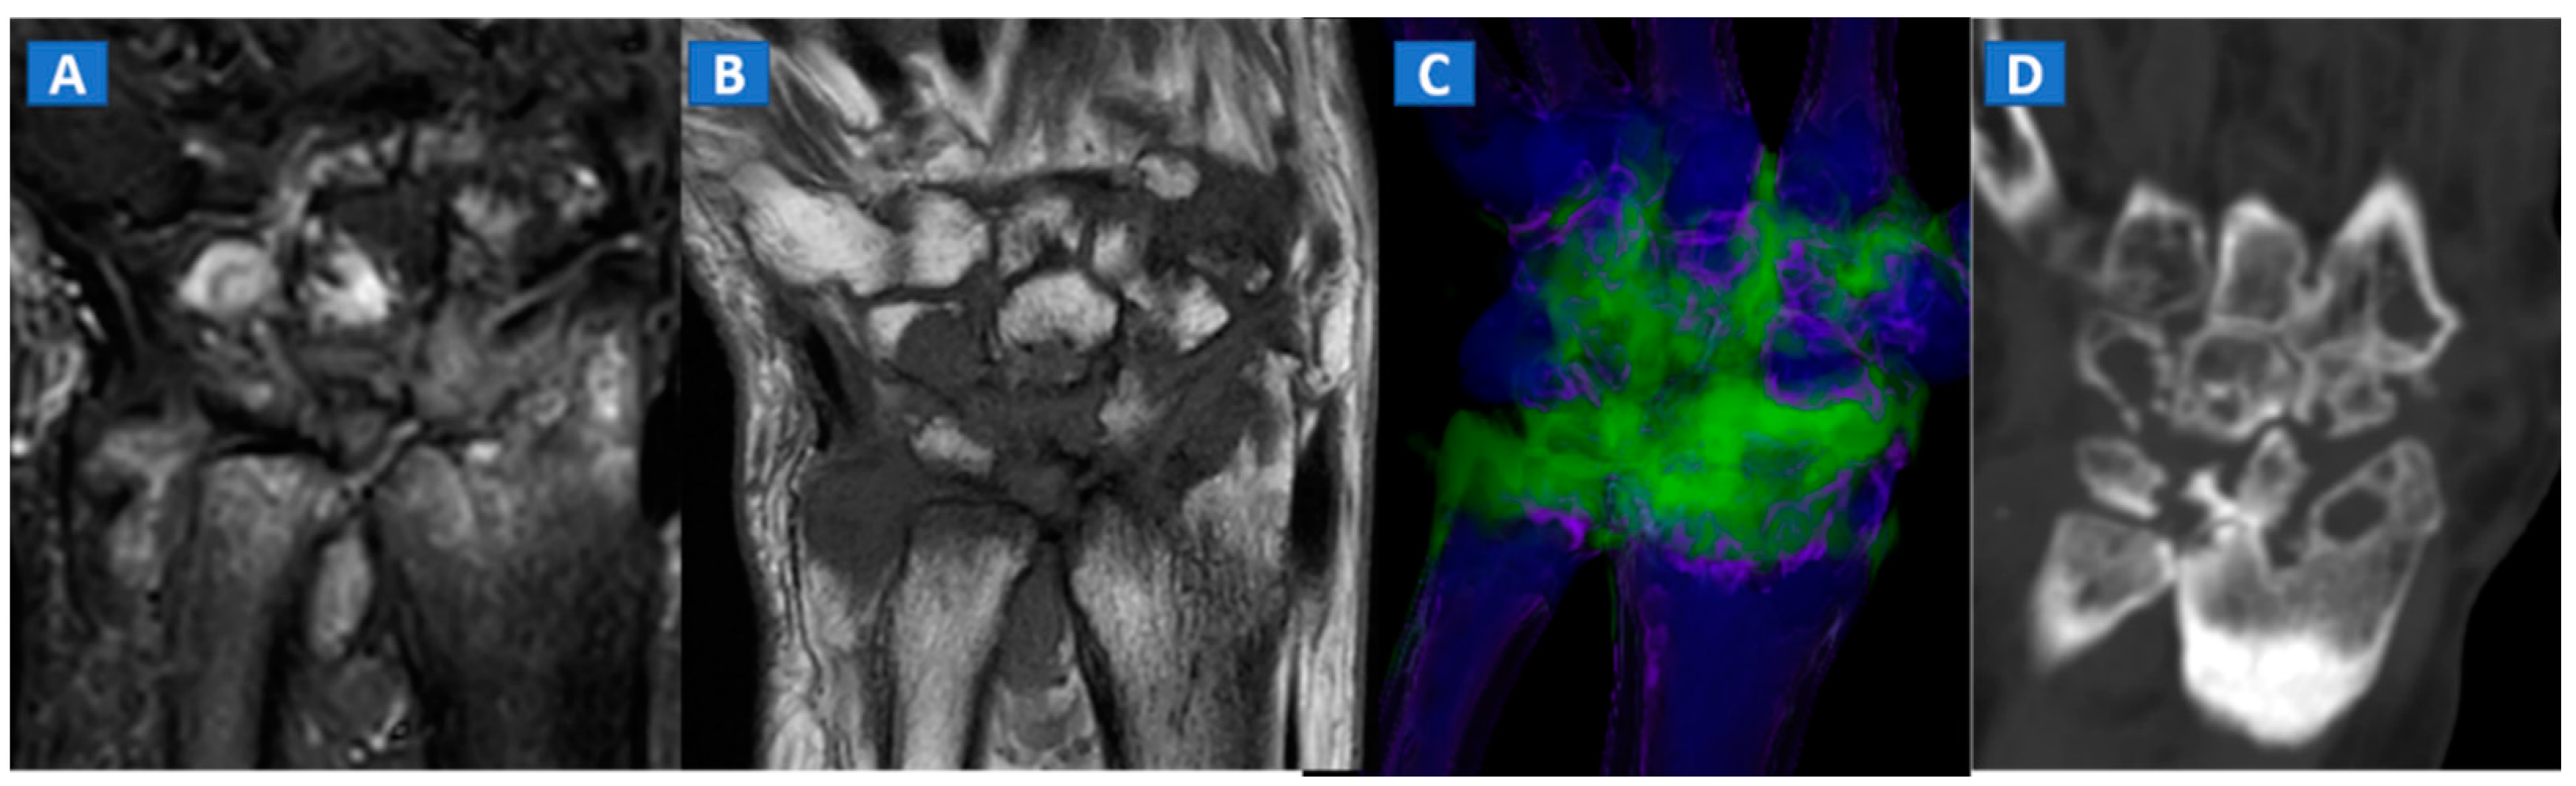

BME represents a common imaging change that is detectable in several inflammatory disorders of the skeletal system, such as autoimmune or septic arthritis. While BME can be used to evaluate the response to therapy in the short term, bone erosions and morphological changes can be used to evaluate the course of disease in the long term (Figure 8 and Figure 9). In cases of advanced inflammatory arthritis, the presence of osteopenia makes it easier for DECT to identify BME, while high resolution CT images can finely identify bone erosions, articular space narrowing and bone remodeling (Figure 8). In painful gout, in addition to identifying tophi, DECT can also assess bone remodeling and detect associated BME [14] (Figure 9). Furthermore, DECT can accurately evaluate BME in patients with sacroiliitis associated with axial spondylarthritis [13].

Figure 8.

A 59-year-old female with advanced rheumatoid arthritis. On the coronal STIR MRI image (A), diffuse BME of the wrist and carpal bone is evident as signal hyperintensity. On the corresponding T1-weighted image (B), advanced erosive changes are apparent. On the 3D coronal DECT image (C), BME is confirmed. The coronal 1 mm standard CT image with soft tissue window (D) allows the depiction of erosive and morphological changes of the carpal bones.

Figure 9.

A 48-year-old female with painful gout. Upon ultrasound study, a hypoechoic tophus is identifiable (A). In the axial CT image with soft-tissue window (B), the tophus shows soft-tissue density (arrow). On the 3D DECT image for gout analysis (C), the tophus is coded in green (thick arrow). Note the presence of tiny additional tophi (thin arrows). On the DECT 3D map (D), BME can be identified on the intermediate cuneiform and on the base of the first metatarsal bone; this may be an additional factor contributing to pain.